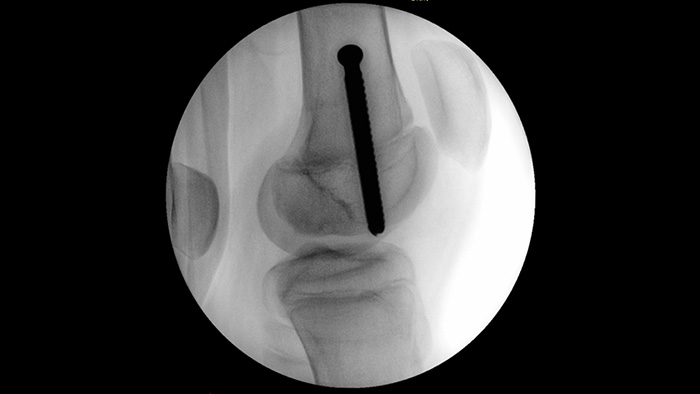

MetalSmart automatically excludes metal artifacts caused by metal implants to provide higher image quality and efficient dose control during orthopedic procedures and patients with metal implants, compared to systems without metal exclusion. BodySmart promotes first-time-right imaging and dose efficiency by automatically adapting the measuring field to the area of interest.